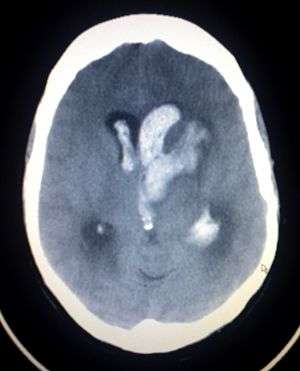

An intracranial hemorrhage, one cause of altered level of consciousness | |

A lowered level of consciousness indicate a deficit in brain function.[4] Level of consciousness can be lowered when the brain receives insufficient oxygen (as occurs in hypoxia); insufficient blood (as occurs in shock); or has an alteration in the brain's chemistry.[3] Metabolic disorders such as diabetes mellitus and uremia can alter consciousness.[11] Hypo- or hypernatremia (decreased and elevated levels of sodium, respectively) as well as dehydration can also produce an altered LOC.[12] A pH outside of the range the brain can tolerate will also alter LOC.[9] Exposure to drugs (e.g. alcohol) or toxins may also lower LOC,[3] as may a core temperature that is too high or too low (hyperthermia or hypothermia). Increases in intracranial pressure (the pressure within the skull) can also cause altered LOC. It can result from traumatic brain injury such as concussion.[11] Stroke and intracranial hemorrhage are other causes.[11] Infections of the central nervous system may also be associated with decreased LOC; for example, an altered LOC is the most common symptom of encephalitis.[13] Neoplasms within the intracranial cavity can also affect consciousness,[11] as can epilepsy and post-seizure states.[9] A decreased LOC can also result from a combination of factors.[11] A concussion, which is a mild traumatic brain injury (MTBI) may result in decreased LOC.